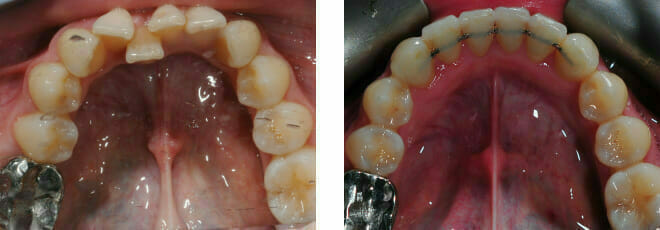

Closing gaps left by extracted teeth, correcting the position of a front incisor tooth trapped behind the bite

In this case the whole smile was affected by a tooth that was missing (a visible gap or hole at the side when smiling) and a tooth at the front that had grown the wrong side of the bite…